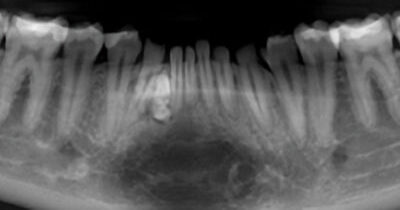

18-year-old boy with lesions in the anterior mandible

An 18-year-old boy was referred to the oral surgeon by his dentist concerning an unusual finding that was discovered during a recent recall exam.